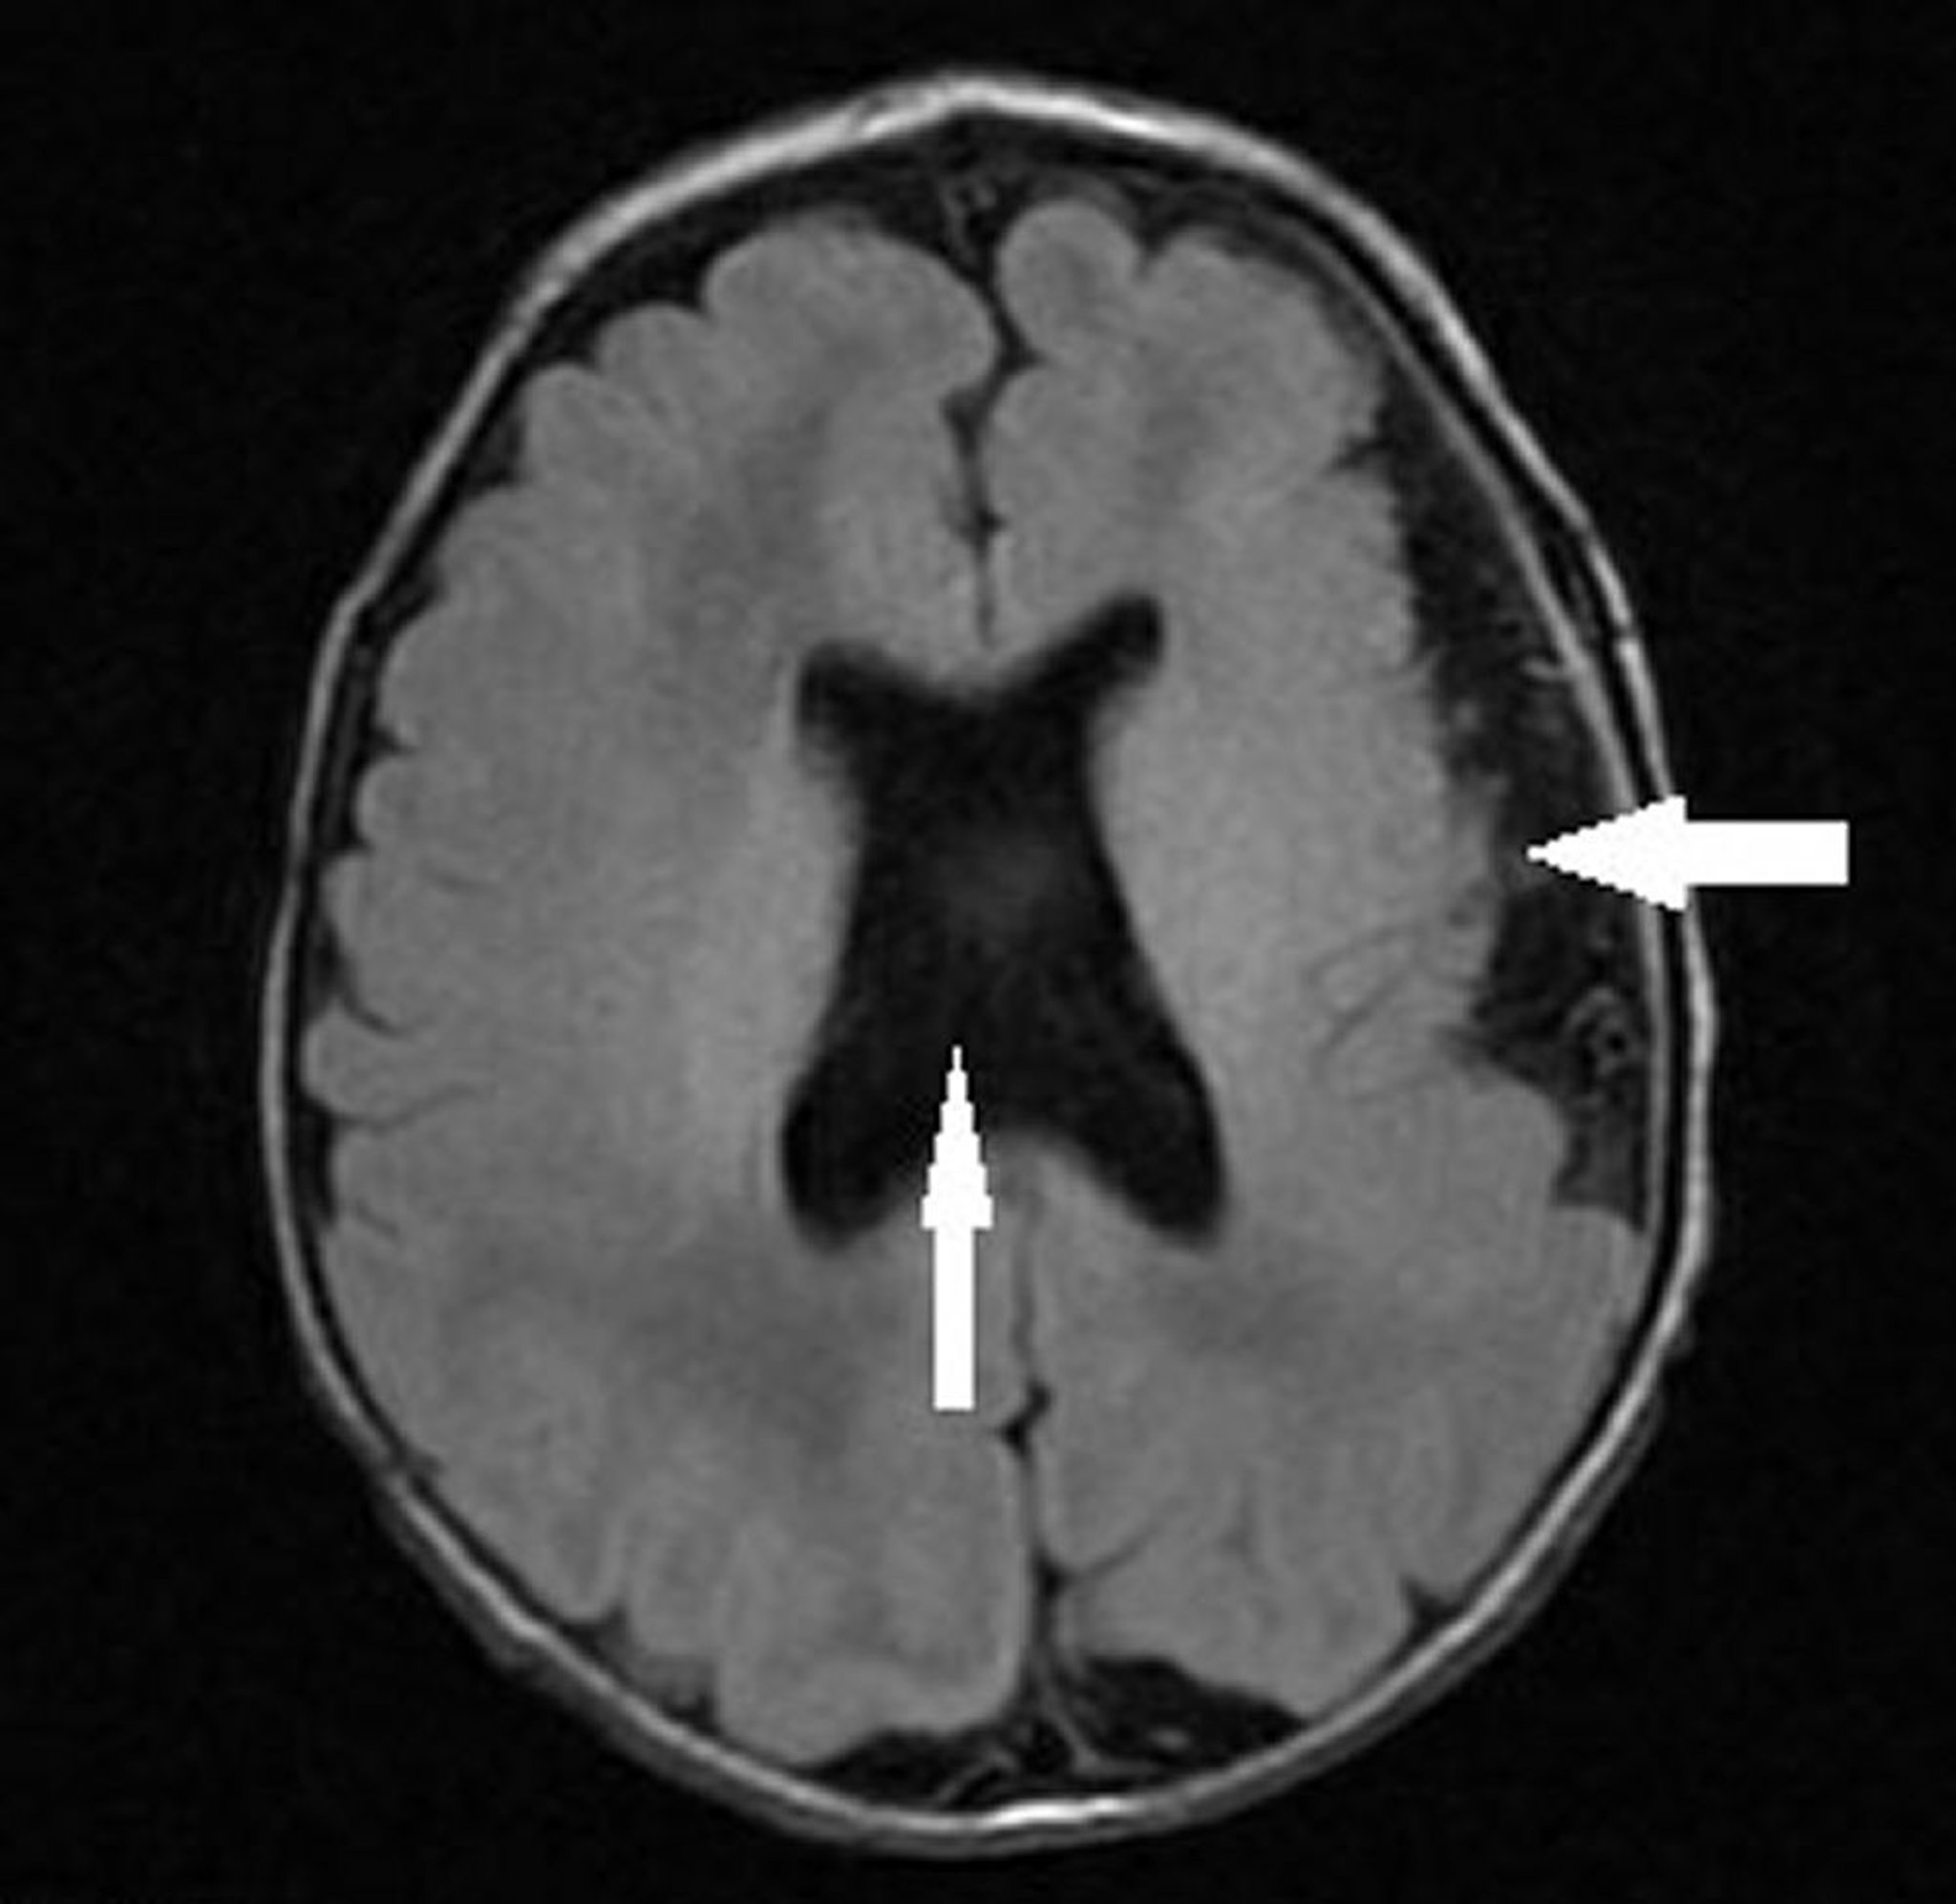

Polimicrogiria con displasia septoóptica

Esta imagen muestra a un lactante con polimicrogiria hemisférica izquierda (flecha hacia la izquierda) y ausencia de septum pellucidum con configuración ventricular anormal (flecha vertical) compatible con displasia septoóptica (hipoplasia del nervio óptico, septum pellucidum ausente o anormal e hipoplasia hipofisaria).

Image courtesy of Stephen J. Falchek, MD.